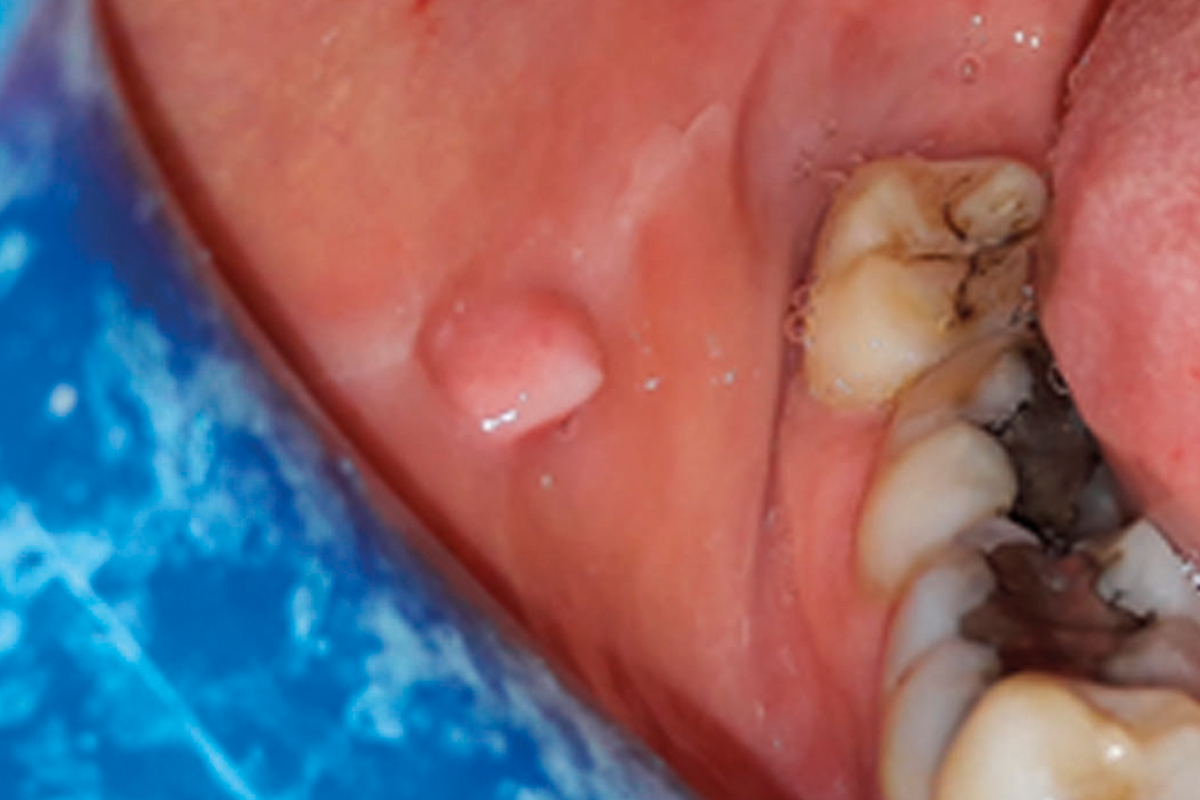

ABLATION D’UN FIBROME SUR LA MUQUEUSE JUGALE